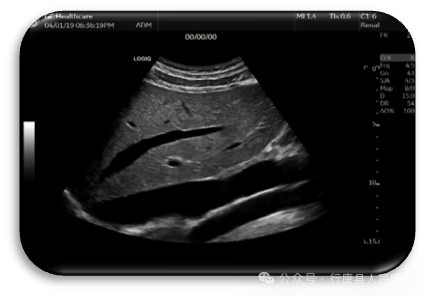

LOGIQ™E11 采用cSound+™全“芯”平台,采用宽波速发射接收信号方式,将射频信号实时存储到本地大数据中,通过GPU直接调用RF信号,利用各种先进算法,将更多的原始数据以高清图像方式呈现出来,解决了传统成像平台成像链长、逐线扫描、逐线接受、单焦点聚焦的技术瓶颈。

声束从不同角度扫描同一像素点,将同—像素点所有回波信号进行合成,使信号得以大大增强,整个声场所有像素合成在瞬间同时完成,全域聚焦,整场图像均匀一致。